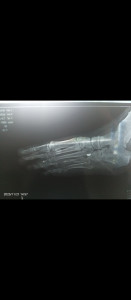

После перелома 4 плюсневой кости с смещением отломков и снятия гипса болит область перелома и большой палец, имеется отёчность.

Здравствуйте. Снимки низкого качества, поэтому детали смещения оценить сложно. После перелома плюсневой кости боль и отёк могут сохраняться несколько недель, особенно если было смещение. Но если боль усиливается или сохраняется долго, нужно повторное рентген-обследование и очный осмотр травматолога, чтобы исключить неполное сращение или посттравматический отёк.